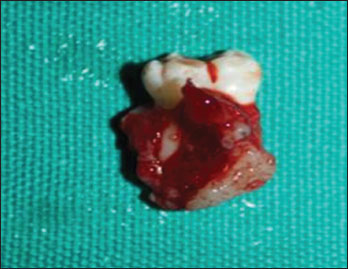

An incisional biopsy was done and it showed epithelial lining with ameloblast-like cells and adjacent connective tissue stroma. There was no luminal proliferation of epithelium, suggestive of intraluminal ameloblastoma [Figure 6]. Following the diagnosis, the parents were informed about the condition and proposed treatment. Surgical enucleation along with chemical cauterization with Carnoy's solution [Figure 7] was done under general anesthesia along with extraction of 47 [Figure 8] considering age of the patient. The patient is under follow-up, with no functional or esthetic complaints. Six months posttreatment, OPG shows signs of new bone formation [Figure 9].

| Figure.8:Surgical specimen with extracted 47